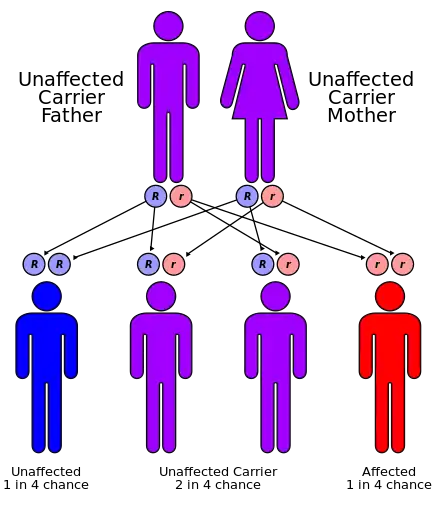

Gitelman syndrome is inherited in an autosomal-recessive manner: one defective allele has to be inherited from each parent.[11]

Gitelman syndrome is estimated to have a prevalence of 1 in 40,000 homozygous people .[1] The ratio of men to women affected is 1:1. This disease is encountered typically past the 1st decade of life, during adolescence or adulthood but can occur in the neonatal period. Heterozygous carriers of the SLC12A3 gene mutations are 1% of the population.[10] Parents with Gitelman syndrome have a low probability of passing the disorder to their offspring roughly 1 in 400 unless they are both carriers of the disease.[9]